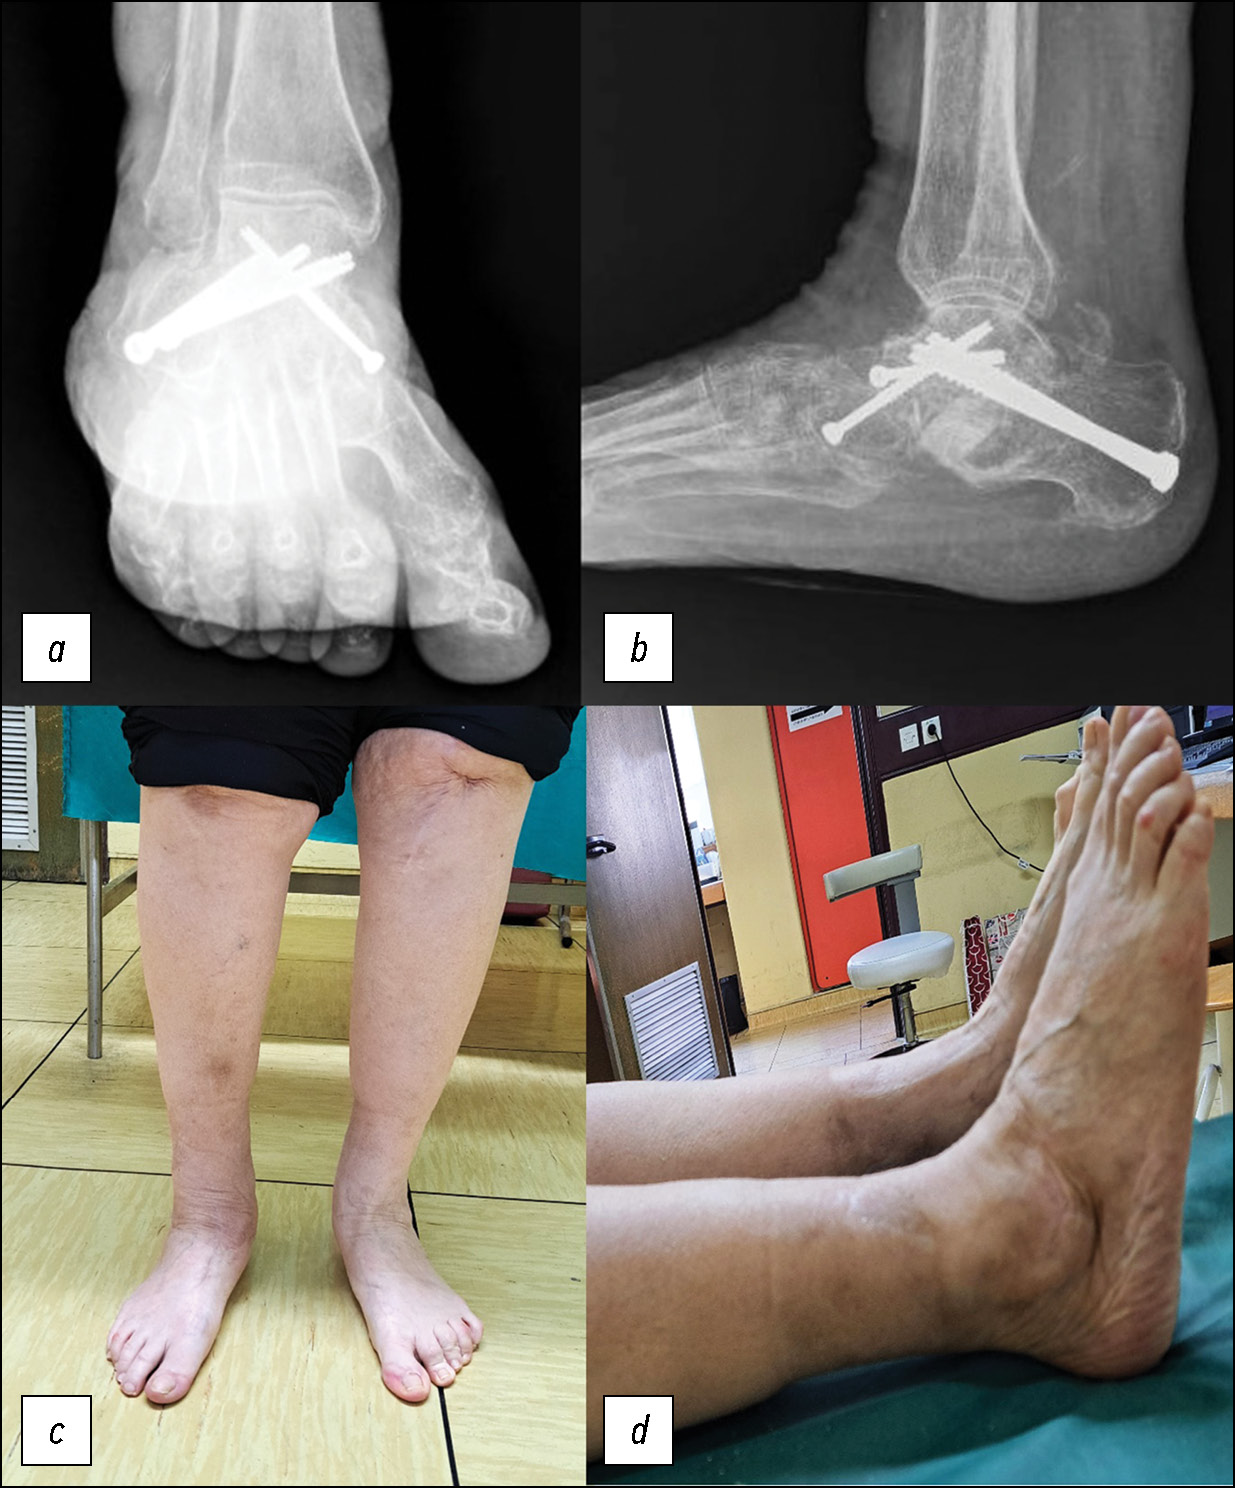

A 55-year-old female patient with rheumatoid arthritis, asthma, and hypertension was referred to the specialist orthopedic clinic by her primary physician due to a 12-month history of progressive right ankle pain and challenges with walking. She denied any history of recent trauma to the affected ankle. Notably, she was diagnosed with acquired flatfoot more than five years ago, which had since deteriorated, resulting in chronic deformity of the left foot and ankle. Upon examination, she exhibited an antalgic gait with signs of discomfort. Although no neurovascular abnormalities were detected, her left foot and ankle demonstrated a pronounced valgus deformity. Notably, the severe valgus deformity caused pronounced skin tension over the medial malleolus, accompanied by skin atrophy and ulceration (Fig. 1). Plain radiographs revealed gross sclerosis and disorganization of foot bones, with medial dislocation of the tarsus, as well as associated lateral dislocation of the calcaneum and cuboid (Fig. 1).

Fig. 1. Clinical image and plain radiography at presentation: anteroposterior (a and c) and lateral (b and d) views.

Considering the chronicity and severity of the bony deformities and soft tissue involvement, a one-stage procedure was planned. To restore pain-free weight bearing and ambulation, talo-calcaneo-cuboido-navicular fusion was performed employing a two-sided surgical approach (Fig. 2). The soft tissue contractures surrounding the bones were released. In the fusion procedure, four screws were utilized to secure the talus, calcaneus, cuboid, and navicular bones together. Initially, a single 4.5-mm cannulated screw was used to perform a talo-navicular fixation. Subsequently, subtalar fixation was achieved employing two 6.5 mm cannulated screws. Finally, a cuboidotalar fixation was established using a second 4.5 mm cannulated screw (Fig. 3).

Fig. 3. Plain radiographs and clinical images six months following the procedure: anteroposterior (a and c) and lateral (b and d) views.

The surfaces of this pathological joint were prepared by excising the cartilage and then filled with frozen cancellous allograft. Eventually, both surgical wounds healed successfully. The lateral wound required an additional two months for complete closure due to the presence of a localized area of skin necrosis. During this period, a non-weight-bearing status was maintained for three months. For the first two months, the patient was immobilized in a back slab; after that, a walking boot was used. Full weight-bearing activity was progressively resumed after three months. Physiotherapy was initiated after 3.5 months. The patient achieved her goal of independent weight bearing and ambulation 4.5 months following the reconstructive process, with satisfactory cosmetic and functional stability in her foot and ankle (Fig. 3).